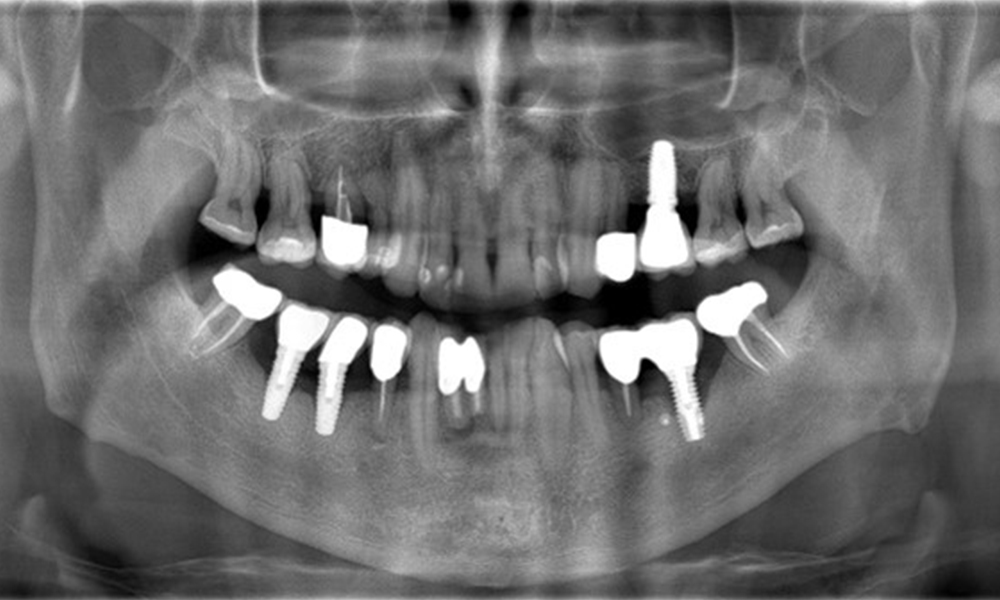

A 52-year-old patient presents at a preventive care session. The patient has no systemic disease and is not taking any medication. He has had various dental treatments and also has two active carious lesions. In addition, the patient has four implants (2nd, 3rd and 4th quadrants). He is revealed to have early periodontal disease (stage IV, grade B). His periodontal condition is stable; a probing depth of Probing depths (ST) of 5 mm is only evident at the implant in region 36. Gingivitis is also identified.

The patient has no particular risk factors with specific dental implications in his medical history. The key factor, therefore, is the requirement in terms of oral health. In this respect, there is evidence of a probing depth of 5 mm at the implant in the 3rd quadrant and, on the X-ray image, increased bone loss. The patient also has currently stable early periodontal disease and two active initial carious lesions.